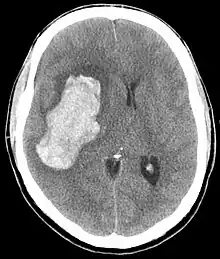

Saignement intra-parenchymateux avec œdème

L'hypertension artérielle maligne est définie par une élévation importante de la pression artérielle s'accompagnant d'une souffrance viscérale (défaillance cardiaque, rénale, neurologique...) avec à l'examen du fond d'œil une rétinopathie hypertensive au stade III ou IV. Il s'agit d'une urgence médicale.